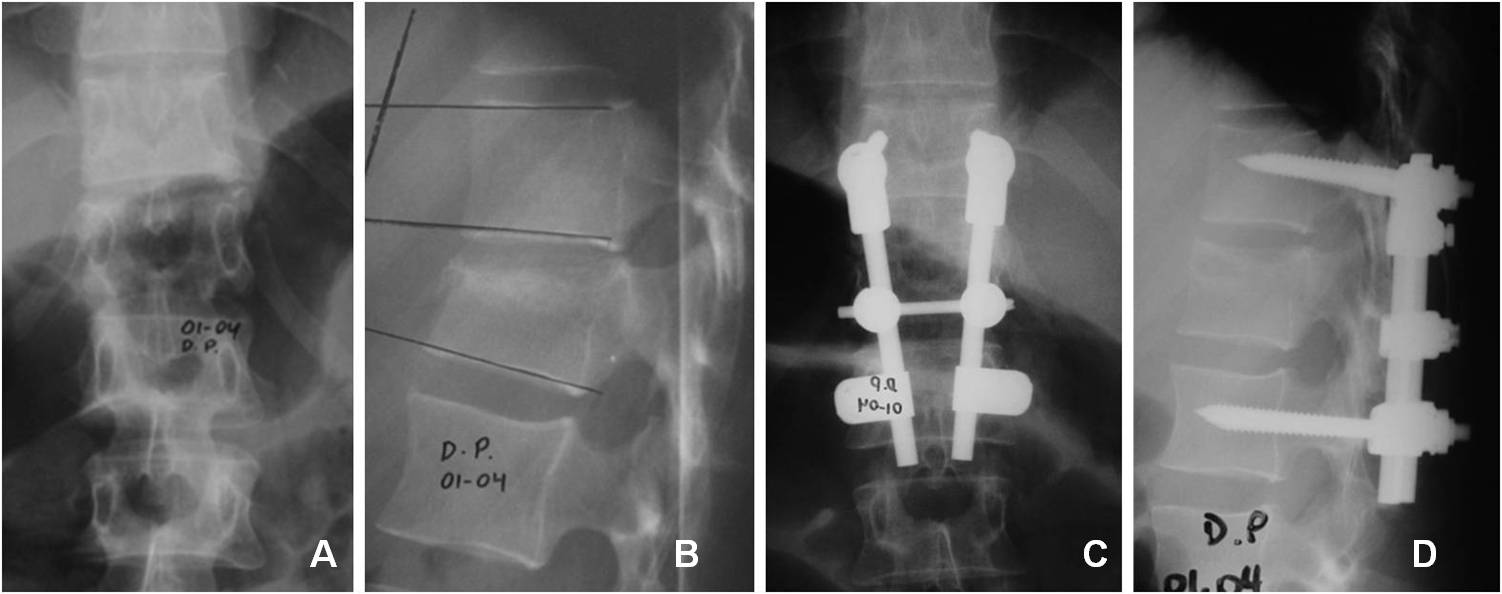

33. Petracchi M, Gruenberg M, Solá C, Ortolán E. Fracturas por estallido en columna dorsolumbar instrumentadas con tornillos

pediculares. Rev Asoc Arg Ortop Traumatol 2003; 68(4): 273-83.

34. Baños Clemente A, Ramirez Villaescusa J, Martinez Castroverde J, Martinez Arnaiz E, Andreés Gonzalez JM. Tratamiento

quirúrgico de fracturas toracolumbares por vía posterior con instrumentación y fusión bisegmentaria. Rev Esp Traumatol 2002;

37(210):84-88.

35. Parker JW. Successful short-segment instrumentation and fusion of thoracolumbar spine fracture. Spine 2000;25(9):1157-69.